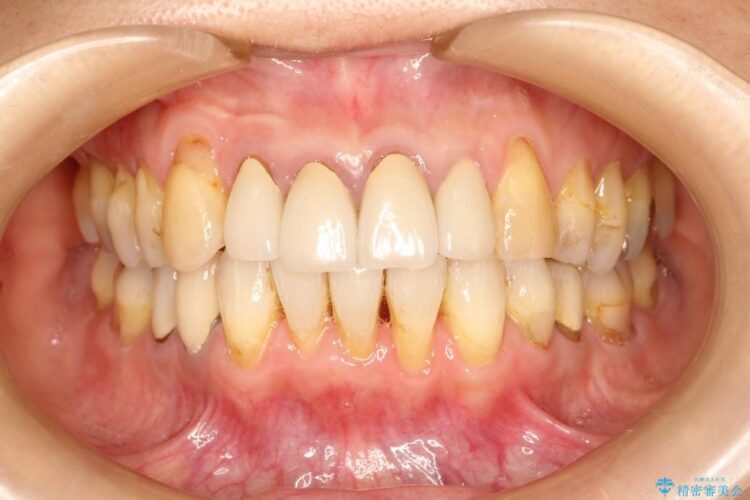

【30代男性】衝撃的なビフォーアフター!クリーニングで見違えるほどの白い歯に

【30代男性】衝撃的なビフォーアフター!クリーニングで見違えるほどの白い歯に ビフォー 【30代男性】衝撃的なビフォーアフター!クリーニングで見違えるほどの白い歯に アフター

歯の着色を綺麗にしたいとご来院されました。